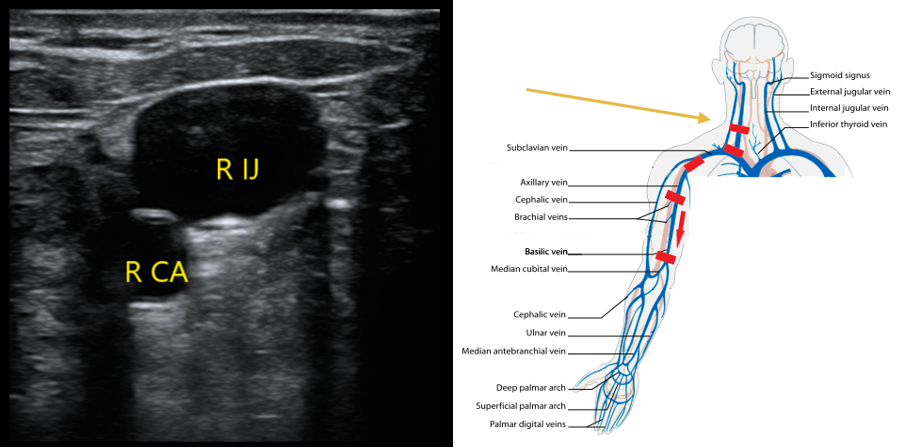

- Upper Extremity Scanning Protocol

- Start in the neck to evaluate the internal jugular vein to the level of the brachiocephalic. With the patient’s head turned to the contralateral side, place the transducer in a transverse orientation over the sternocleidomastoid muscle. You should be able to identify the IJ over the carotid artery (CA) (Fig. 3). Compress if you do not see echogenic material in the lumen of the IJ.

- Figure 3. Appearance of right internal jugular and right CA. Most caudal red rectangle indicates orientation of transducer.